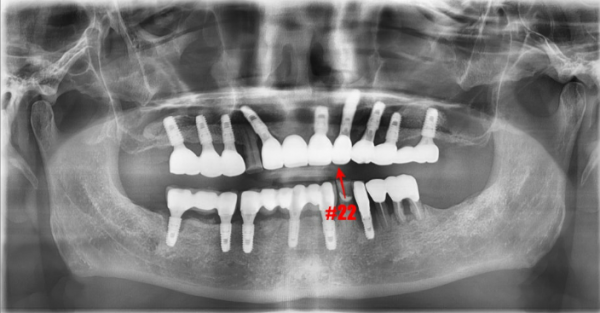

특히 앞니 부위에 문제가 생긴다면? 그 걱정은 더욱 커질 수밖에 없겠죠.

일반적으로 임플란트 주위에 세균 감염이 발생하여 치조골이 손상되면,

기존 임플란트를 제거한 후 상당한 기간을 기다려야 합니다.